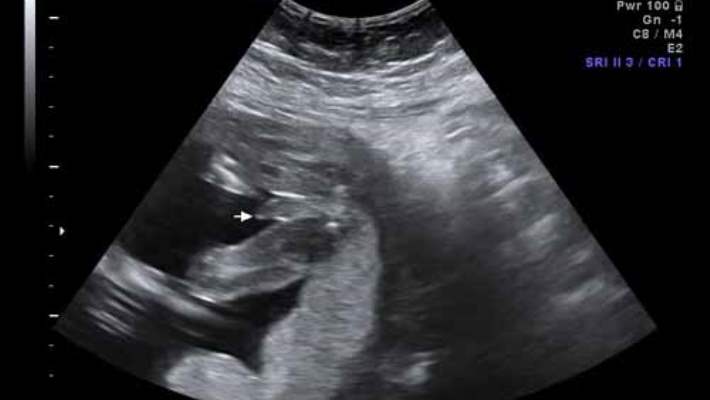

Test sonuçlarınız pozitif çıkarsa sağlık bakım uzmanınız, gebelik süresini ve bebek sayısını doğrulamak için ultrasonu önerebilir. Ultrason sırasında sağlık bakım uzmanınız aynı zamanda bebeğinizin gelişimini değerlendirebilir, plasentayı inceleyebilir ve olası anomalileri tanımlayabilir.

Çoğunlukla anormal test sonuçları, amniyosentez gibi kesin teşhise yönelik daha başka testleri düşünmeniz için bir davettir. Amniyosentez dörtlü tarama testinden daha güçlüdür ve çok az düşük yapma riski taşır, fakat bebeğinizin sağlığına dair daha iyi bilgi verir. Ultrason çoğunlukla spina bifida ve anensefaliyi tespit etmek için kullanılmasına rağmen bir invazif test kromozomla ilgili bozuklukları teşhis etmenin tek yoludur.